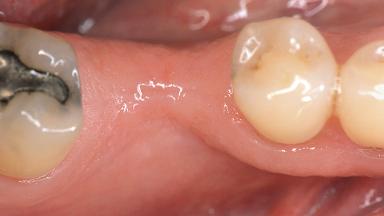

In 1983, a 51-year-old non-smoking patient was referred for the treatment of moderate chronic periodontitis. At the initial examination, 47% of sites exhibited probing depths of 4 to 6 mm. Periodontal therapy consisted of initial periodontal treatment including oral-hygiene instructions and supra- and subgingival debridement, followed by periodontal surgery to eliminate residual pockets.